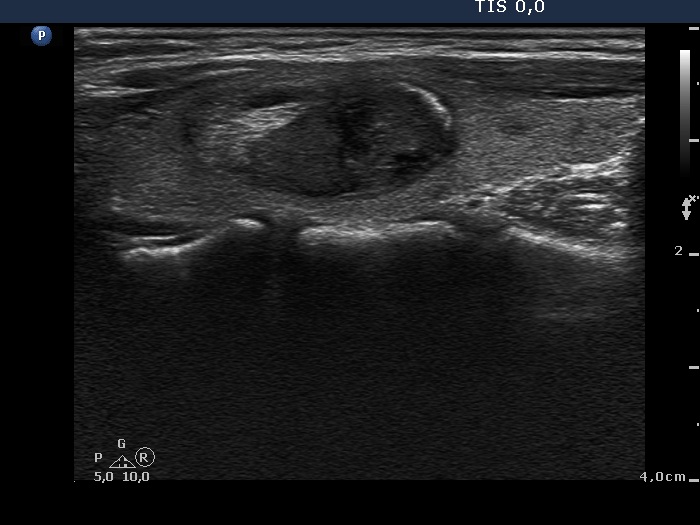

Ethanol sclerotherapy: other examples - Case 3: treatment of a gelatinous thyroid cyst

Six months after the therapy (ultrasonographic picture 2)

Right lobe, longitudinal scan.